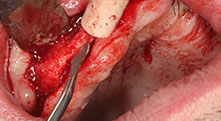

Piezomed B6

Алвеоларният гребен е разделен на две чрез пиезо хирургия (инструмент: Piezomed B6). Имплантите са поставени наведнъж и периимплантологичната кост е допълнително изградена чрез GBR техника.